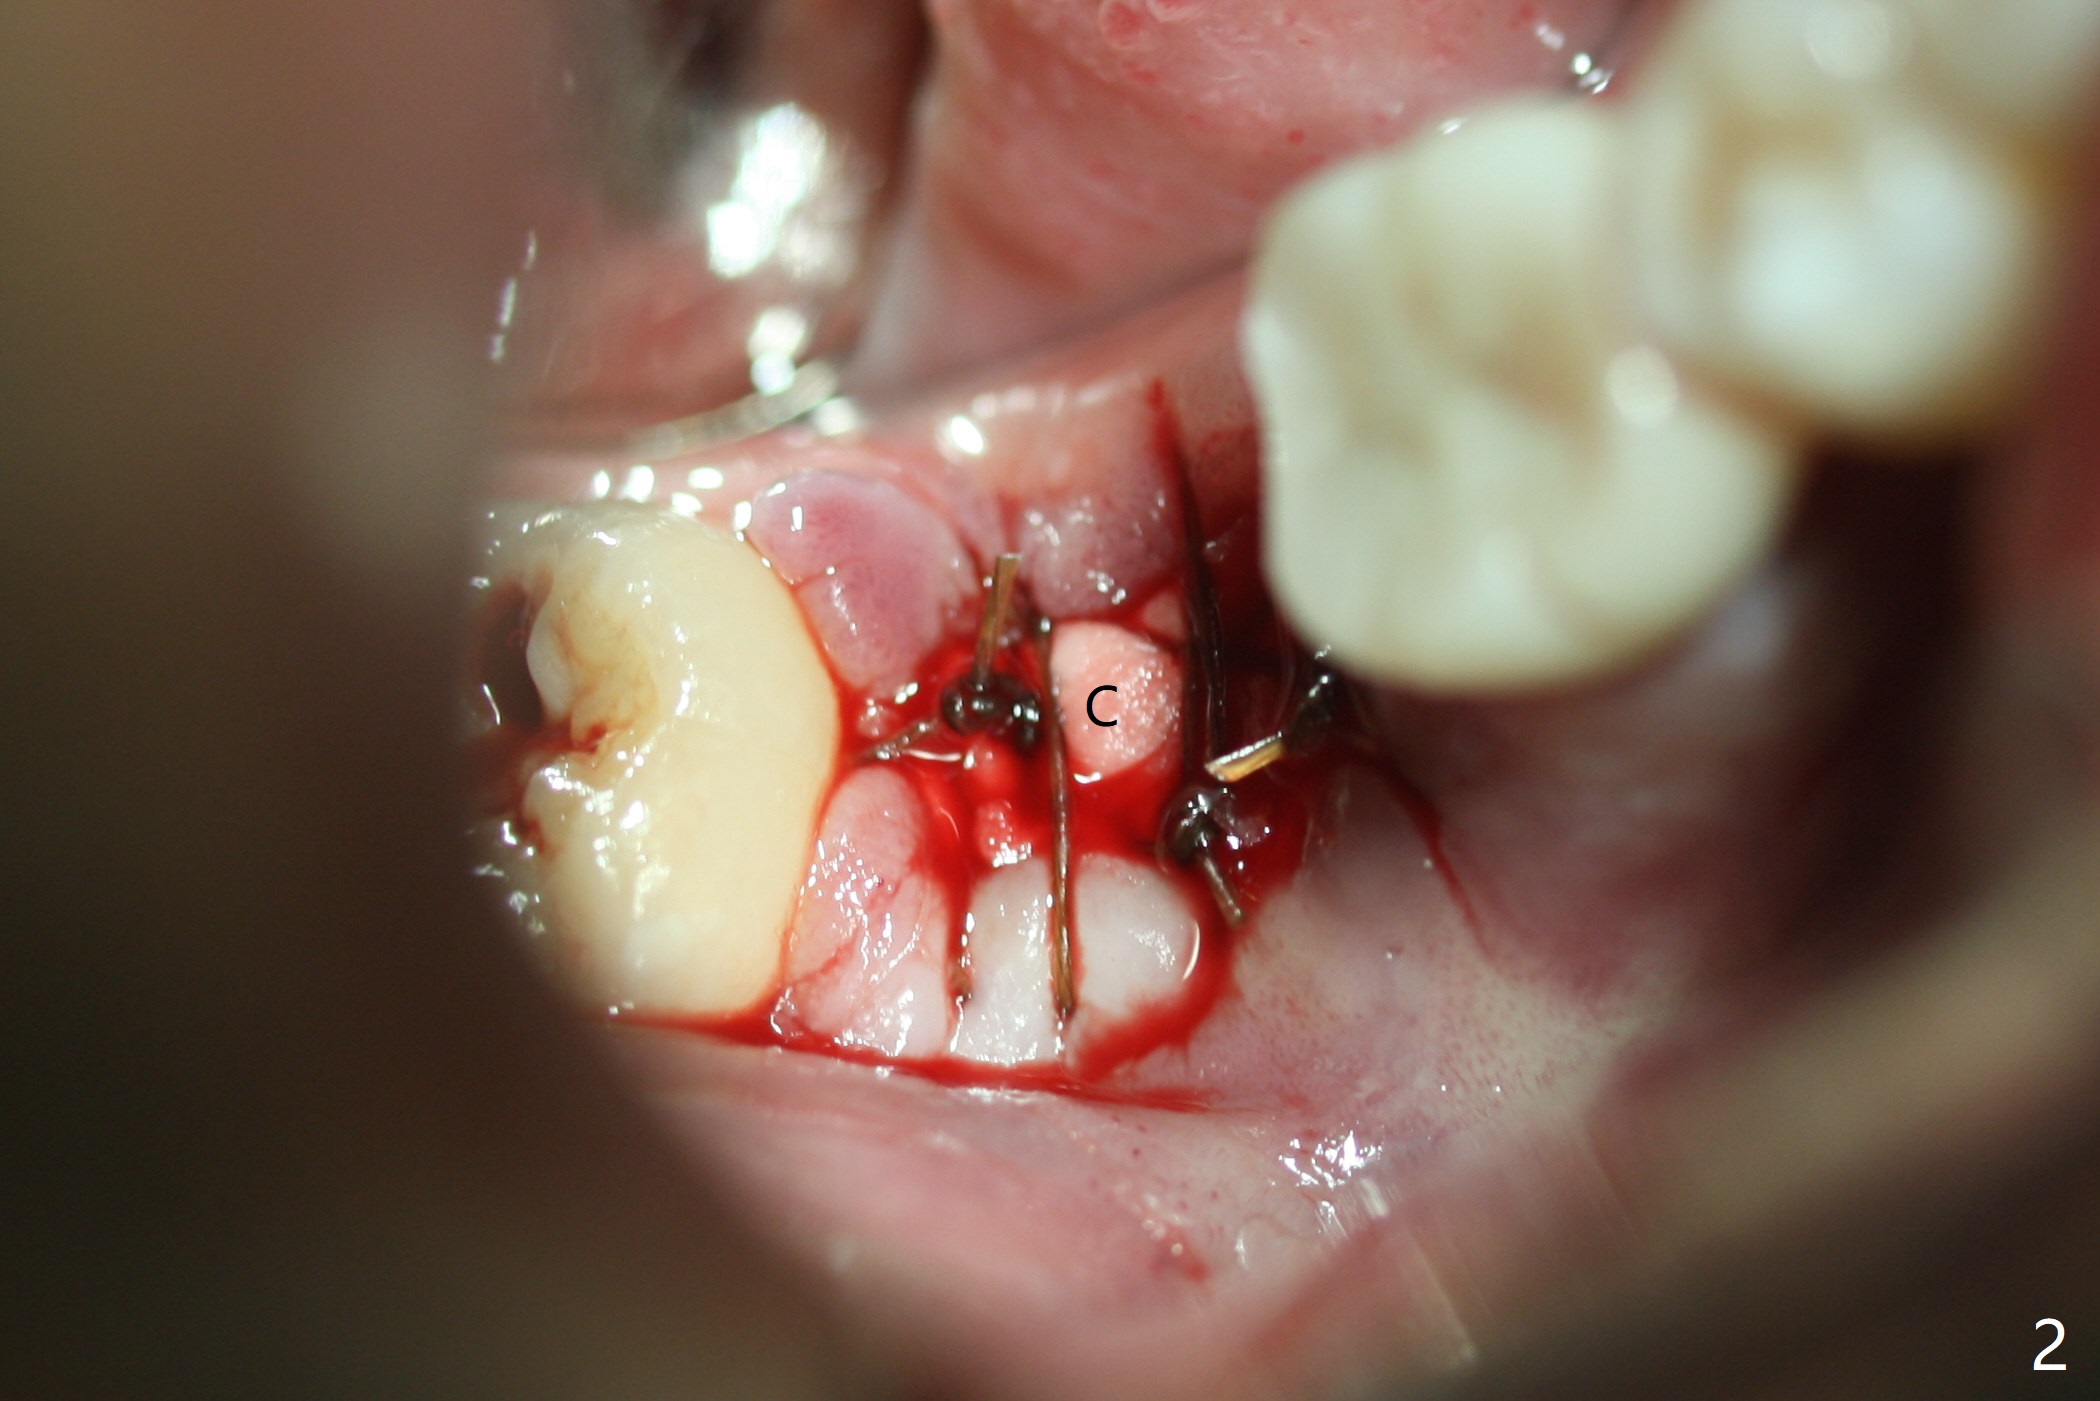

Although the bony socket is shallow, the soft tissue one remains deep at #31 with gingival recession (Fig.1 *). The deep soft tissue socket with hemorrhage after extraction presents difficulty in debridement of granulation tissue apically. After placement of allograft (Fig.3 *) and overlying collagen membrane (Fig.2 C), the socket is closed with 4-0 Chromic gut suture. In fact, there is ~ 2 mm granulation tissue left (Fig.4 red (yellow line: upper border of the Inferior Alveolar Canal)). To reduce socket shrinkage, the tooth #32 is not extracted. The collagen membrane has lost 1 week postop (Fig.5). More sutures should have been used, preferably using Human Amnion Chorion Allgraft as a membrane. The latter promotes wound healing. The bone graft also seems to have lost in 8.5 months (Fig.6). A short implant will be placed mesially and obliquely (Fig.7).